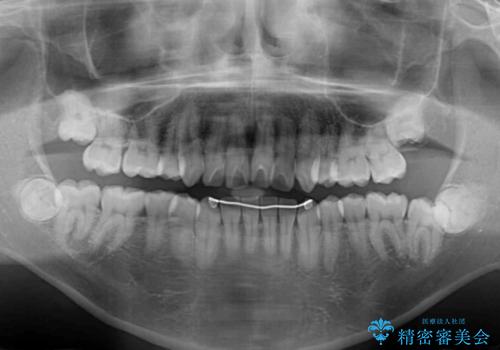

- 学生時代に抜歯矯正した歯列が後戻りしてきたとのことで来院された患者様です。

舌の突出癖が原因で上顎前歯が前方に移動したと考えられたため、舌のトレーニングを徹底して行っていただきながら、後戻りを解消していくこととしました。

ワイヤー矯正ということで、上顎大臼歯を後方に移動するための補助装置を併用して、積極的に前歯を引っ込めていくこととしました。

上顎歯列全体がスムーズに後方移動でき、1年で治療を終えることができました。